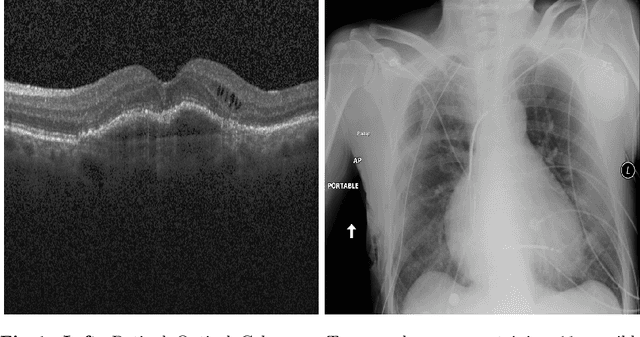

Multi-label classification (MLC) problems are becoming increasingly popular in the context of medical imaging. This has in part been driven by the fact that acquiring annotations for MLC is far less burdensome than for semantic segmentation and yet provides more expressiveness than multi-class classification. However, to train MLCs, most methods have resorted to similar objective functions as with traditional multi-class classification settings. We show in this work that such approaches are not optimal and instead propose a novel deep MLC classification method in affine subspace. At its core, the method attempts to pull features of class-labels towards different affine subspaces while maximizing the distance between them. We evaluate the method using two MLC medical imaging datasets and show a large performance increase compared to previous multi-label frameworks. This method can be seen as a plug-in replacement loss function and is trainable in an end-to-end fashion.